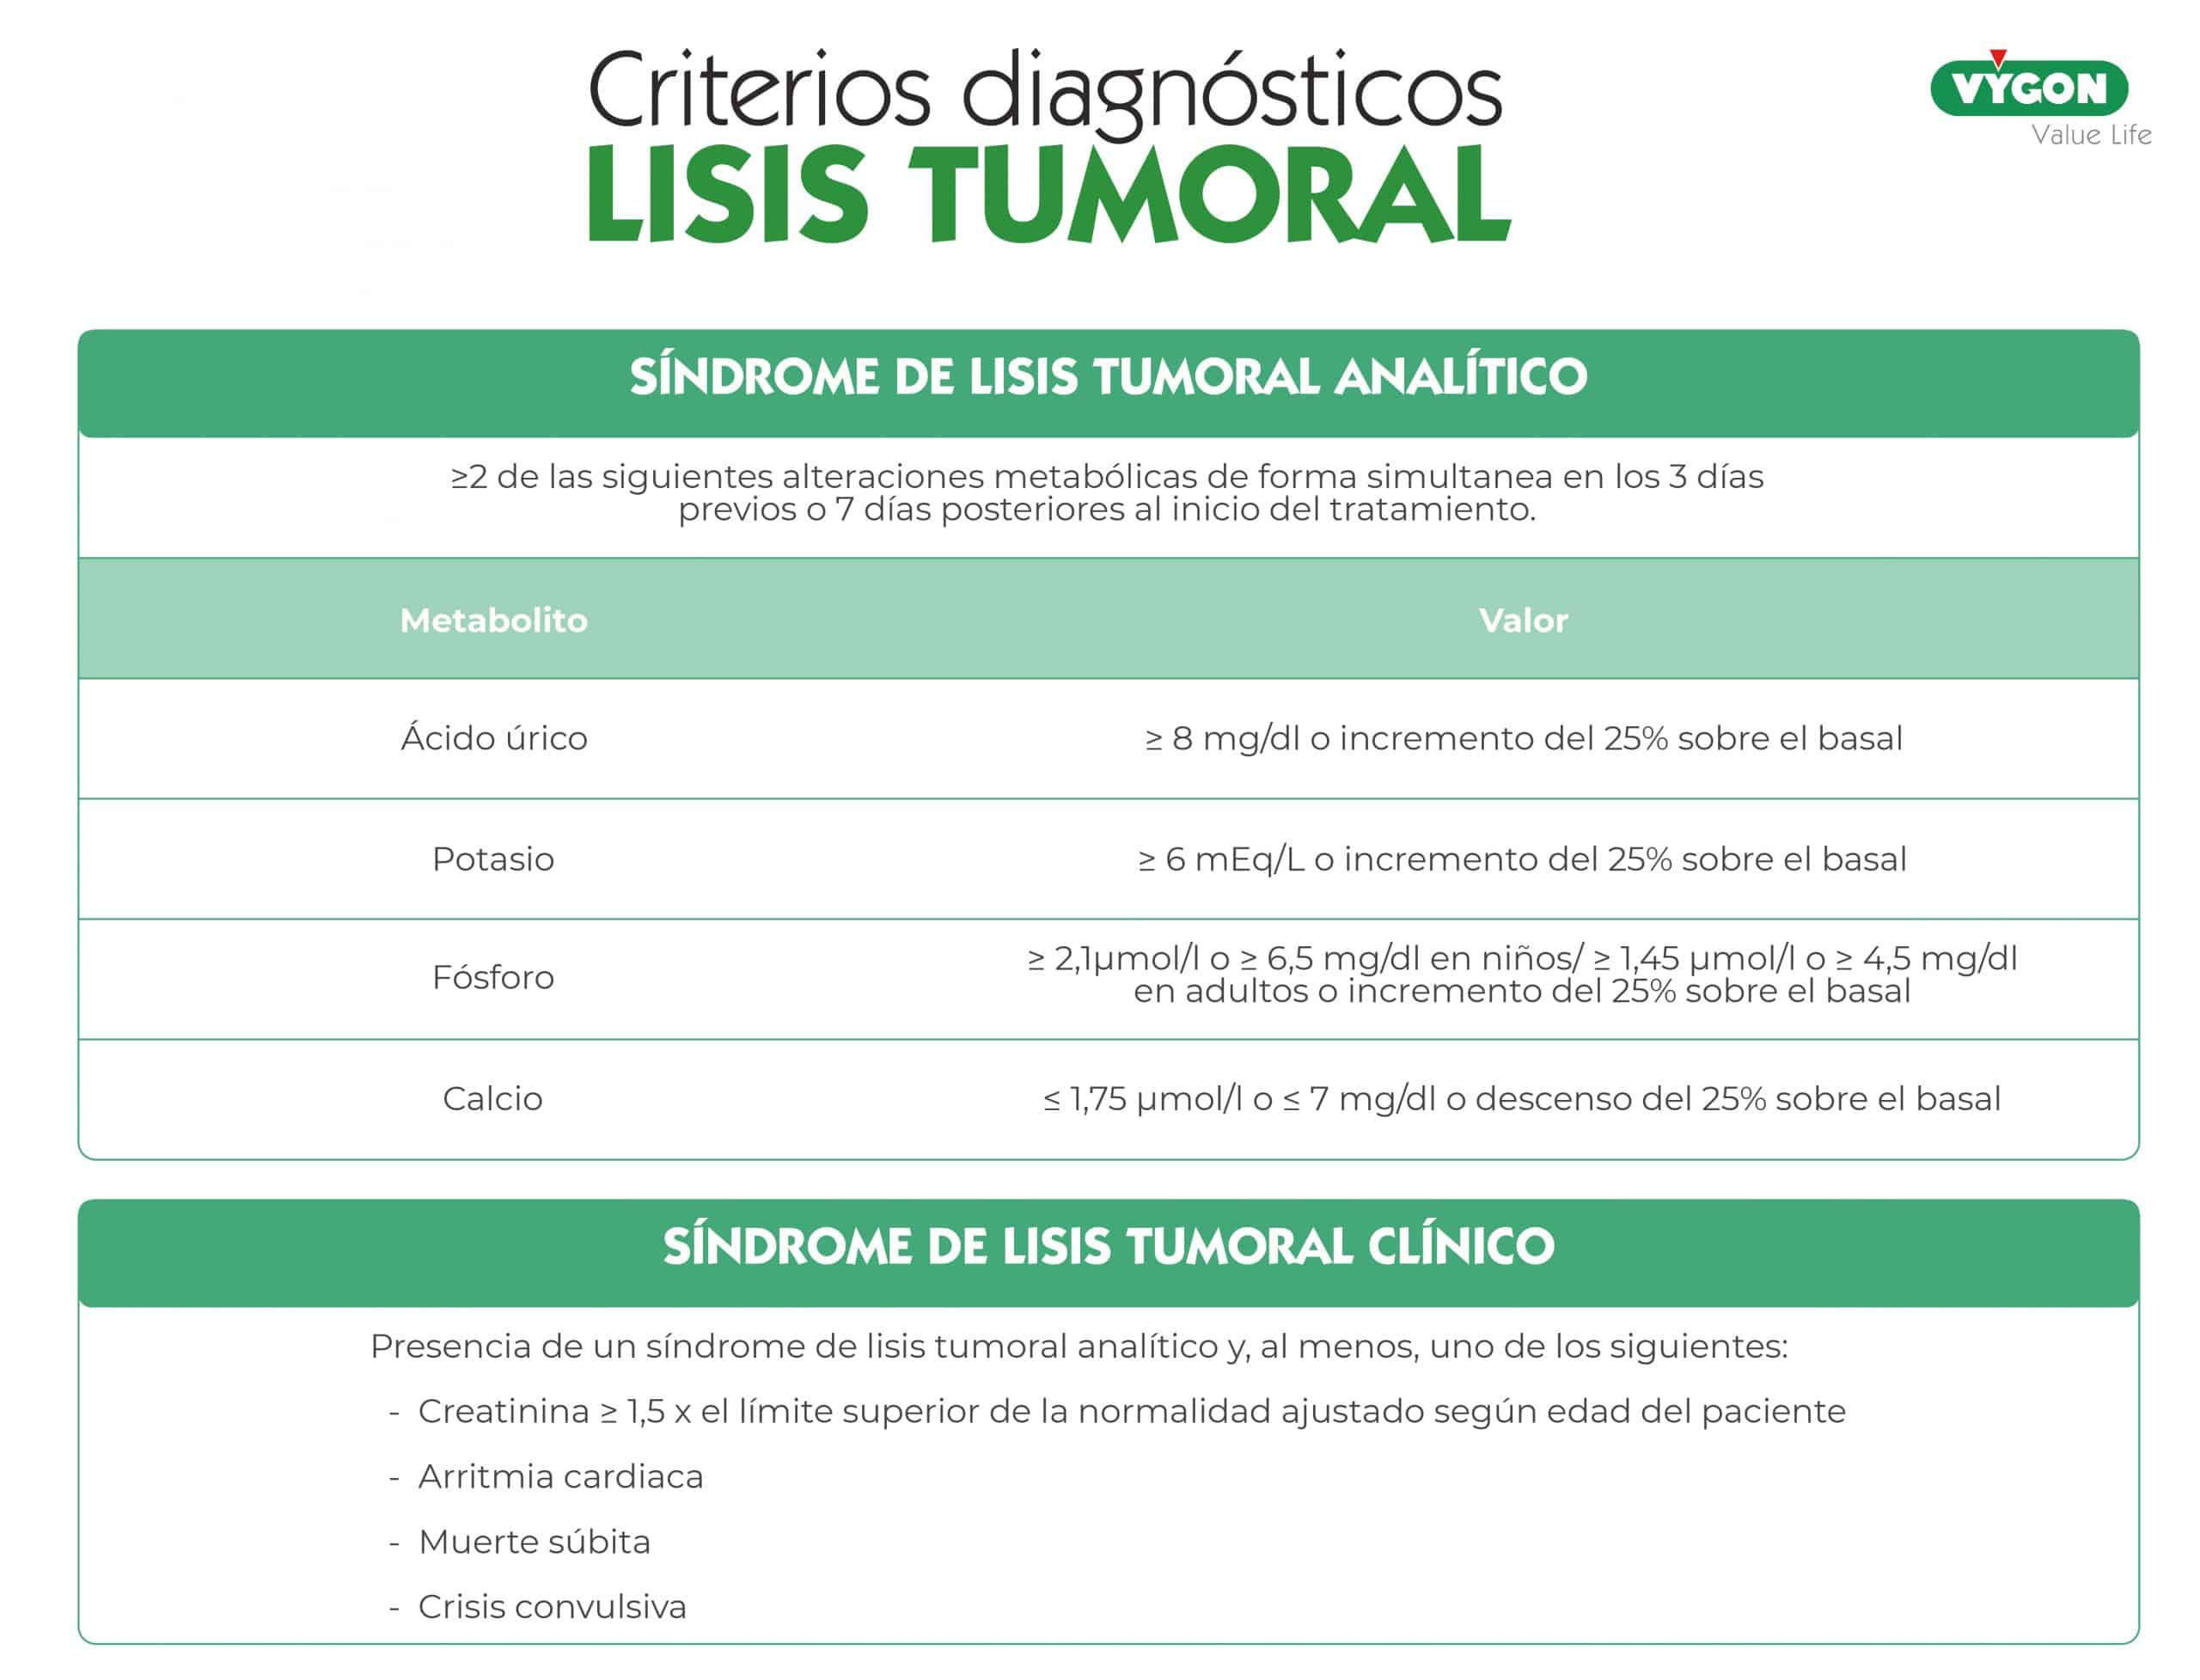

Criterios diagnósticos

En los criterios diagnósticos del síndrome de lisis tumoral se incluyen alteraciones metabólicas y cuadros clínicos.

Las alteraciones metabólicas vienen definidas principalmente por los niveles de:

- Ácido úrico

- Potasio

- Fósforo

- Calcio

Con respecto al síndrome de lisis tumoral clínico, ha de cumplir como mínimo uno de los siguientes escenarios:

- Fallo renal definido por una creatinina ≥ 1,5 por el límite superior de la normalidad ajustado según edad del paciente

- Arritmia cardiaca

- Muerte súbita

- Crisis convulsiva